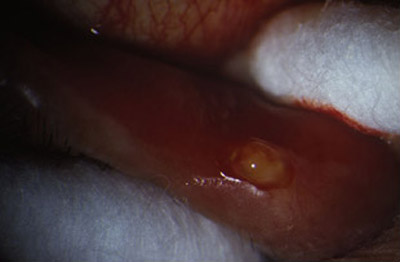

La presencia de un canalículo superior o inferior eritematoso, turgente, a veces doloroso, lleno de abundante material purulento caseoso, de color verde claro, caracteristicamente producido por estos microorganismos, nos lleva al diagnóstico.

El punto lagrimal inferior puede estar vertical, en un ligero ectrópion medial. Al realizar presión sobre el canalículo afectado entre dos hisopos de algodón, y repitiendo esta maniobra varias veces en la lampara de hendidura, se puede obtener abundante material caseoso sin dificultad.